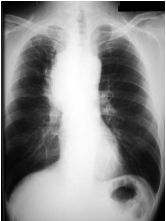

55 60 歲男性因近日來呼吸急促、頭痛及數度暈厥被送來急診。理學檢查發現 頸靜脈擴張,眼眶周圍、臉部及上肢皆有水腫現象。胸部 X-光片檢查如圖。 請問最可能的診斷是:

(A)肺動脈栓塞(Pulmonary embolism) (B)升主動脈剝離(Ascending aortic dissection) (C)心包膜填塞(cardiac tamponade) (D)腎病症候群(Nephrotic syndrome) (E)上腔靜脈症候群(SVC syndrome)